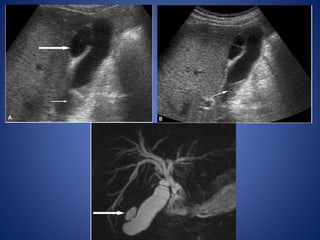

Ultrasound Echogenic triangular cordsign Tubular echogenic cord of fibrous tissue seen in the porta hepatis at ultrasonography and is relatively specific in diagnosis of biliary atresia. It is defined as more than 4 mm thickness of echogenic anterior wall of right portal vein (EARPV) measured on a longitudinal ultrasound scan. Gallbladder ghost triad Atretic gallbladder, length less than 19 mm Irregular or lobular contour Lack of smooth/complete echogenic mucosal lining with indistinct wall Larger hepatic arterial calibre

• 64.

Positive of triangularcord sign = thickness of EARPV > 4 mm on a longitudinal scan 5.1mm 5.4mm

• 65.

Length= 1.6mm Irregular orlobular contour Lack of smooth/complete echogenic mucosal lining with indistinct wall Gall bladder ghost triad